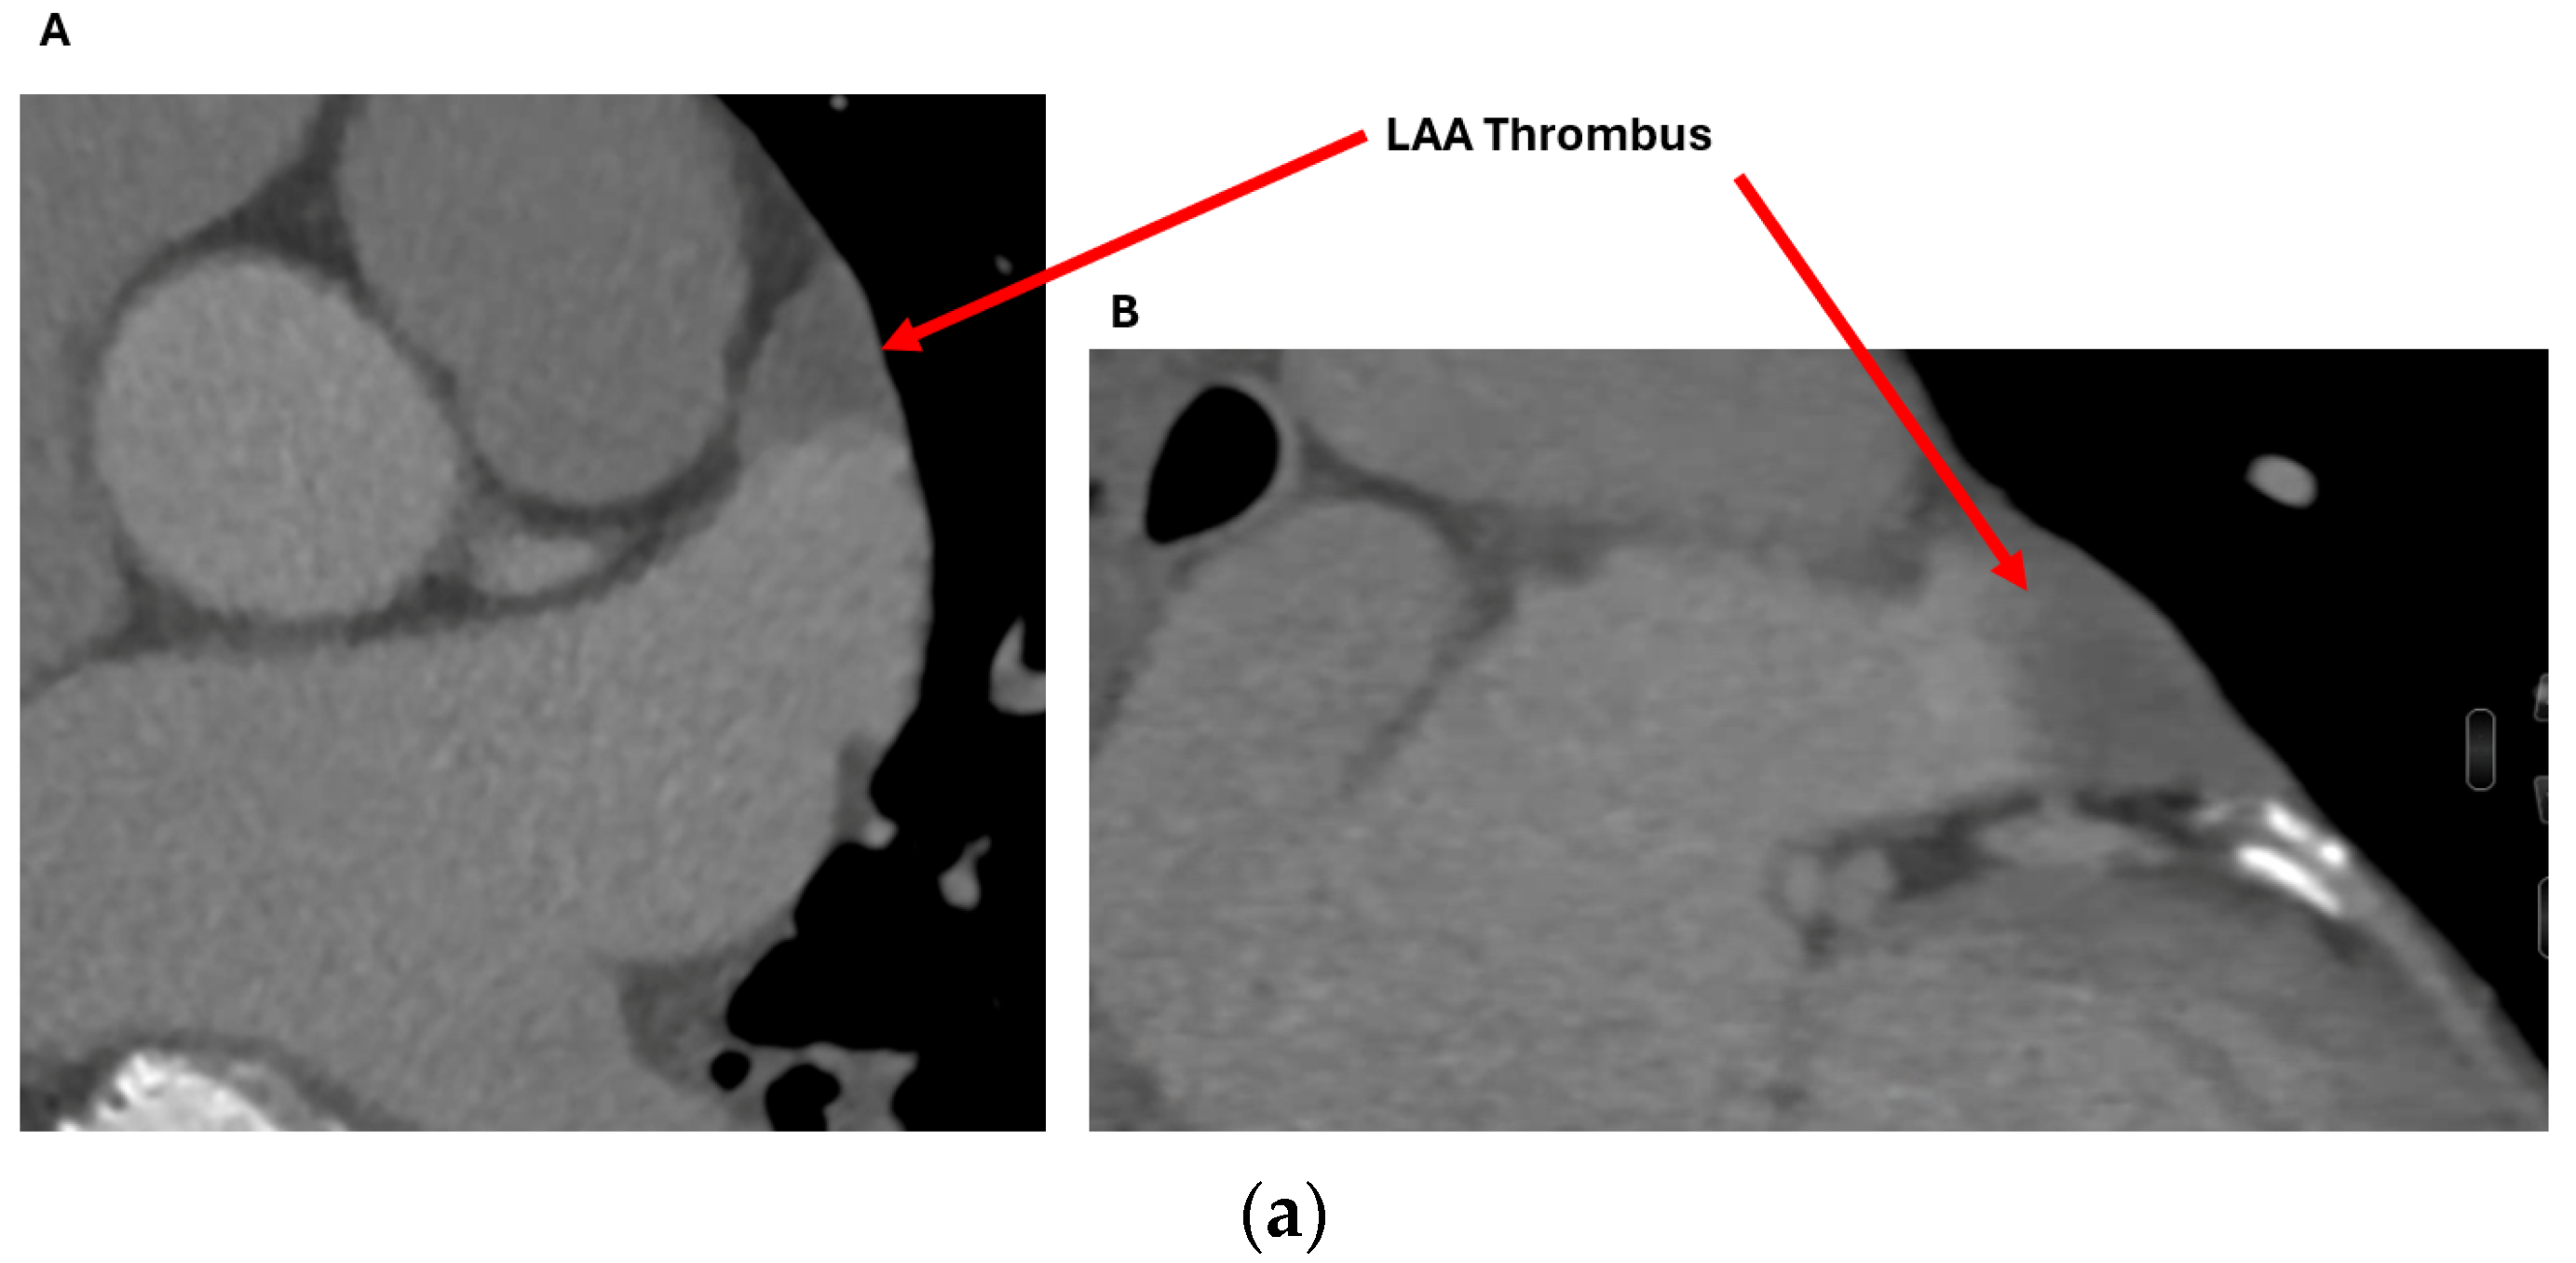

2.1.1. Anatomical Contraindications

2.2.1. LAA Thrombus Assessment